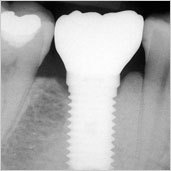

İmplant kaybedilen diş kökünün yerine çene kemiğine yerleştirilen, titanyum malzemesinden üretilmiş küçük bir parçadır. İmplant ayakta tedavi kapsamında lokal anestezi altında yapılan bir operatif işlemdir. Günümüzde yapay diş kökleri diş hekimleri tarafından hemen hemen her boşluğu doldurmakta kullanılabilmektedir.

Tedavi süreci hastanın kemik yapısına ve genel durumuna göre farklılık gösterebilir. Çok iyi olgularda implant operasyonları 15 dakika içerisinde tamamlanabilmektedir. Ayrıca uygulanacak implant adedi de tedavi sürecini belirlemede önemli bir etkendir. Genellikle operasyon sonrasında 2. ayda implantın üzerine dişler yerleştirilerek tedavi tamamlanır.